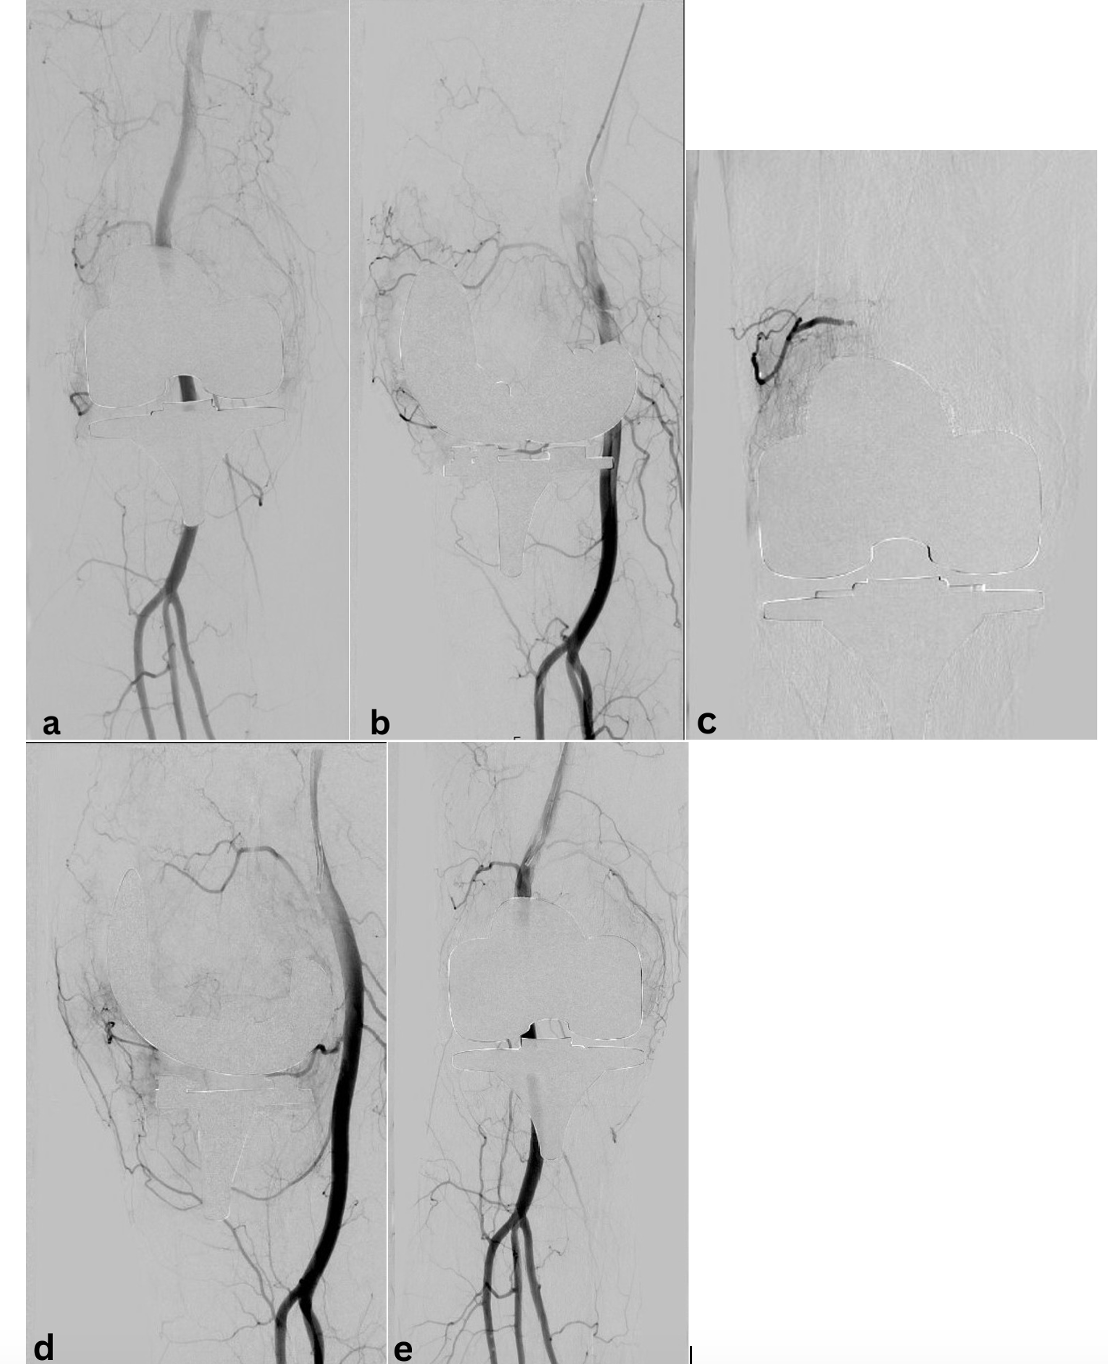

Angiogram performed after selective coil embolization of the

Angiogram performed after selective coil embolization of the How Is An Embolization Performed What is an embolization procedure? Catheter embolization places medications or synthetic materials called embolic agents through a catheter into a blood vessel to block blood. An embolisation is a procedure used to stop the blood flow to a certain part of your body by blocking a small. What is a vascular embolisation? Embolization involves injecting medications or embolic agents (designed. How Is An Embolization Performed.